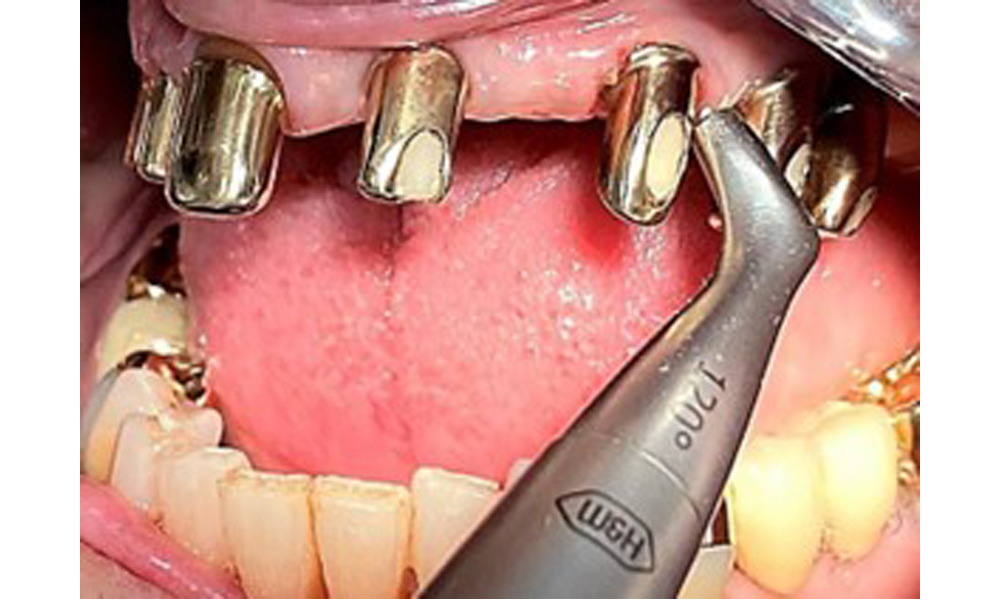

Фронтален изглед с поставена горночелюстна протеза.

Фиг. 1: Фронтален изглед с поставена горночелюстна протеза.

На пациентката е поставена комбинирана подвижна горночелюстна телескопична протеза преди повече от 25 години (фиг. 1, фиг. 2, фиг. 3) и тя е много доволна от протезите си. Пациентката има адекватна фиксирана протеза за долната челюст (фиг. 4).

Денталните открития са следните: Комбинирани снемаеми протези на импланти и телескопични протези, поддържани от зъби, на импланти 15, 13, 21, 23, 24, 25 и зъб 11 (фиг. 1, фиг. 2, фиг. 3). Пациентът е снабден с фиксирана долночелюстна протеза. Над зъби 37-34 и 45-47 бяха налични адекватни мостове (фиг. 4), краищата на коронките бяха интактни и нямаше активен кариес. Върху зъб 43 имаше композитна пломба с маргинална празнина. Имаше рецесия на долната гингива, която разкриваше от 1 до 3 mm от кореновата повърхност. Това се отнася и за 11.